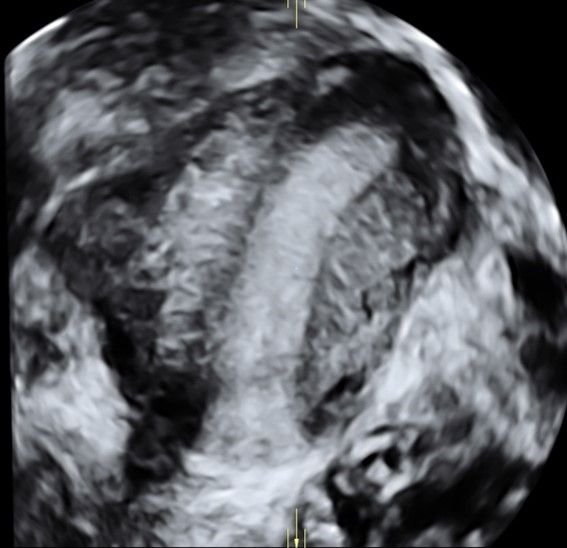

Современные экспертные УЗИ сканеры дают возможность проводить исследования всех органов в 3D. Это позволяет, используя полученный массив данных, получать диагностические сечения в любой плоскости, недоступной для обычного 2D УЗИ. Наиболее интересной является фронтальная. Например, визуализация полости матки. Диагностическая возможность выявления пороков развития превосходит все другие методы (рентгеновские и МРТ). Метод также позволяет уточнить положение ВМК (спирали) в полости матки, расположение миоматозных узлов, расположение плодного яйца на малых сроках, полипов. Сегодня современное экспертное ультразвуковое исследование невозможно без использования 3D УЗИ.